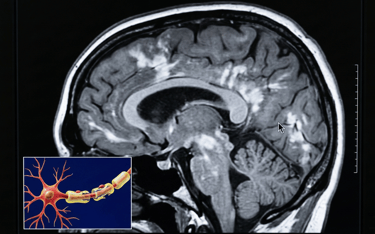

La neurología es la especialidad que estudia el cerebro, la médula espinal, los nervios y los músculos, es decir, el sistema que dirige cómo piensas, te mueves, sientes, duermes y recuerdas. Cuando algo cambia en este “centro de control”, los síntomas pueden ser muy variados: desde dolor de cabeza, mareo o adormecimiento, hasta temblores, cambios en la memoria, dificultad para hablar, problemas de equilibrio o crisis convulsivas. La buena noticia es que, en muchos casos, identificar a tiempo las señales y dar seguimiento ayuda a reducir riesgos y a mantener calidad de vida.